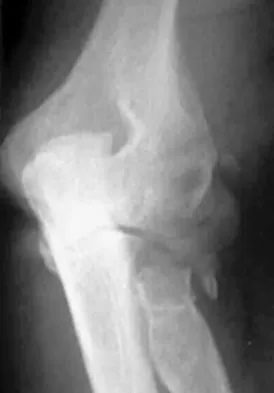

A 65-year-old woman fell onto her outstretched right arm and immediately had pain. She has a history of osteoporosis. Examination of the right arm reveals lateral arm swelling, ecchymosis, and she is unable to move the elbow due to pain. Her neurovascular status is intact. Radiographs are shown in Figures 14a and 14b. Appropriate treatment should include

Comminuted, displaced radial head fractures (Hotchkiss type 3) require anatomic metallic radial head arthroplasty to regain function. Radial head excision has led to catastrophic sequelae including chronic wrist pain, elbow instability, and proximal radius migration. Immobilization, internal fixation, or anconeus arthroplasty are not recommended at this time because of the potentially poorer outcomes. Hotchkiss RN: Displaced fractures of the radial head: Internal fixation or excision? J Am Acad Orthop Surg 1997;5:1-10.